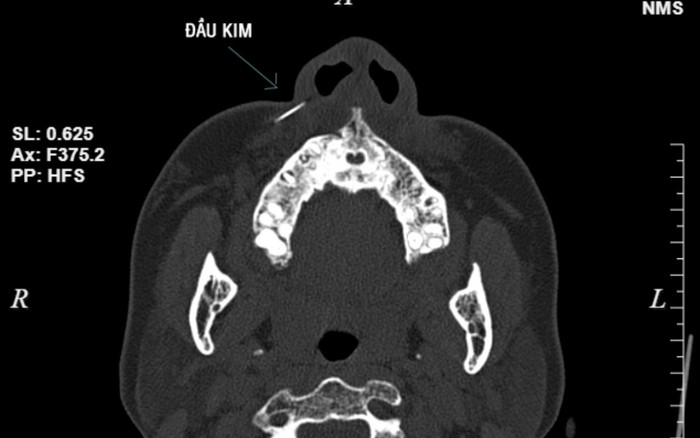

Chụp CT scanner, cho kết quả hình ảnh dị vật khoảng 1cm, vị trí phần mềm cánh mũi phải. (Ảnh: BVCC).

Sau khi tiếp nhận bệnh nhân, các bác sĩ tiến hành chụp CT scanner, cho kết quả hình ảnh dị vật khoảng 1cm, vị trí phần mềm cánh mũi phải, chỉ định thủ thuật lấy dị vật cho bệnh nhân.